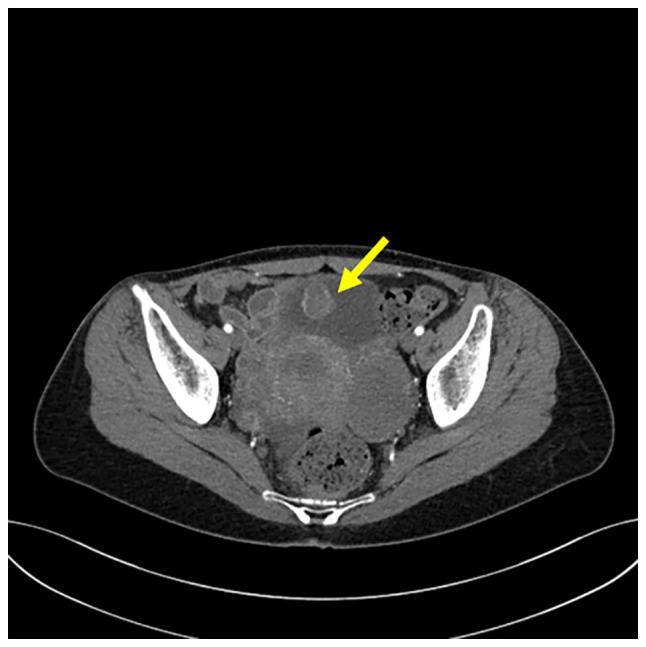

炎性肌成纤维细胞瘤(IMTs)是一种罕见肿瘤,具有肌成纤维细胞分化特征,常伴有间变性淋巴瘤激酶(ALK)基因重排。已证实在泌尿道中发现的一部分IMTs含有纤连蛋白1(FN1)-ALK基因融合。在本病例报告中,呈现了1例膀胱中存在FN1-ALK融合的IMT病例,并对其临床病理特征进行了回顾。一名45岁女性因肉眼血尿被转诊至忠北国立大学医院。膀胱镜检查发现膀胱内有一实性肿块。该患者随后接受了经尿道病变切除术。肿块由星状和梭形肌成纤维细胞组成,这些细胞排列成疏松束状,伴有黏液样背景和混合性炎性浸润。免疫组织化学分析显示肿瘤细胞波形蛋白、细胞角蛋白AE1/AE3和ALK呈阳性,结蛋白呈局灶性阳性。随后采用靶向二代测序来鉴定FN1-ALK融合。迄今为止,该患者已接受门诊随访18个月,无肿瘤复发迹象。总之,总共已确定FN1几乎仅在泌尿生殖系统IMT病例中作为ALK融合伴侣[13例膀胱IMT(包括本病例)和2例子宫IMT]。在本病例中,发现FN1-ALK融合涉及ALK外显子19和FN1外显子23。相比之下,其他大多数具有ALK融合的IMTs涉及ALK外显子20,而涉及ALK外显子18或19的ALK融合仅在泌尿生殖系统IMTs中有报道。因此,涉及ALK外显子18或19的FN1-ALK融合可能是膀胱中出现的一部分IMTs所特有的。